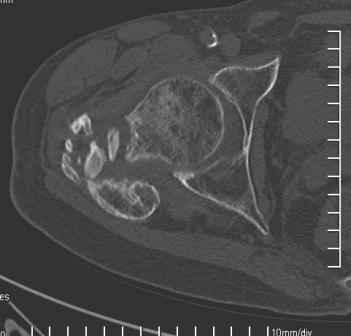

Сросшийся со смещением чрез-подвертельный перелом

Больной Н. 44 года травма 1,5 года назад июнь 2008 года чрез-под вертельный перелом правого бедра. Во время лечения у больного развился алк. делирий, проводилось консервативное лечение перелома.

Осмотрен 30.10.09.

Беспокоят боли, укорочение конечности. Укорочение 3 см. Ногу поднимает, сгибание ограничено, ротационные движения в полном объеме. На КТ перелом сросся за счет костной мозоли. Что делать?

Протез? Если «да» Можно ли обойтись стандартной ножкой Corail?

Или межвертельная остеотомия?